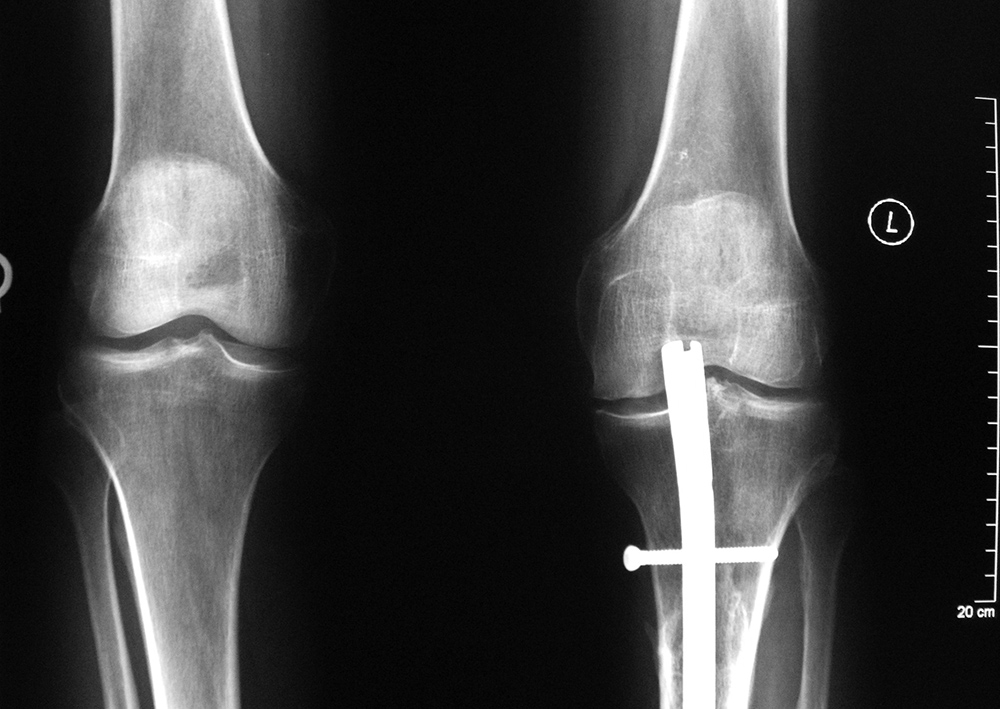

Left knee antegrade intramedullary rod displacement into knee joint |

| 41 year-old man with chronic left femoral neck fracture and fracture of superior cannulated fixation screw. The partially visualized intramedullary nail is for an old femoral shaft fracture. |